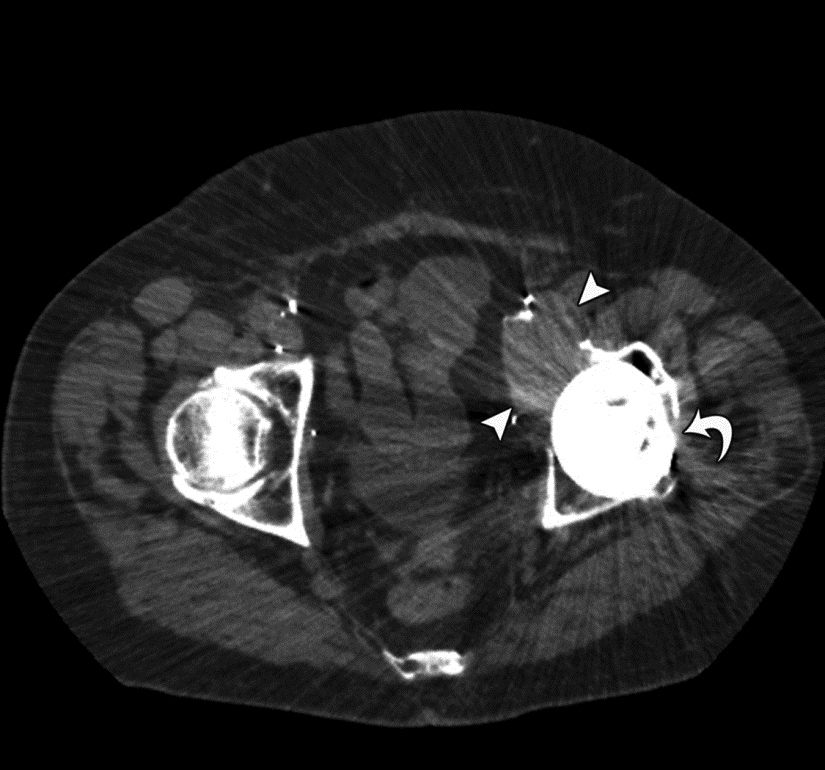

Periprosthetic osteolysis represents a host of conditions, including small-particle disease, mechanical hardware loosening and periprosthetic infection, manifested by bone destruction surrounding implanted hardware (Figure 11). Imaging may not be able to differentiate the underlying cause of osteolysis, but identifying its extent and potential associated soft tissue involvement provides useful information to the referring physician.

In the case of infection, which is uncommon, nuclear medicine studies, aspiration or biopsy may be required to confirm the diagnosis. Small-particle disease results from implant wear, leading to particle shedding and provocation of a histiocytic response, which manifests as bone destruction. The most common cause of small-particle disease is polyethylene wear, and most patients remain asymptomatic until extensive bone loss is present (Ohashi, 2009; Naudie, 2004). Radiographic evaluation of small-particle disease can be limited by location of the lesion, position of the hardware, and patient body habitus. In particular, evaluation of peri-acetabular particle disease can be challenging due to the above factors. In such cases, CT may be indicated to determine the presence and volume of osteolysis prior to hardware revision (Figure 12) (Chiang, 2003; Claus, 2004).

Evaluation of osteolysis requires attention to optimized metal artifact reduction with use of a soft tissue kernel and wide window settings (> 6000) to best visualize periprosthetic lucency (Ohashi, 2009). Focal lucency greater than 2 mm or interval increase compared to prior CT studies typically indicates osteolysis and should prompt clinical evaluation for an underlying cause (Ohashi, 2005; Taljanovic, 2003). It is important to note that comparison of periprosthetic lucency measurements between radiographs and CT may differ and small differences should not be relied upon for diagnosing osteolysis. CT may also be used for prosthesis templating prior to revision arthroplasty in cases of severe bone loss and remodeling.

Figure 11 Figure 12 Figure 13 Figure 14

Hardware infection Small particle disease Hardware failure Liner displacement

Small Particle Disease. Axial CT image of the pelvis demonstrates left total hip arthroplasty with adjacent cortical disruption (curved arrow) and destructive soft tissue lesion (arrowheads) arising from the anteromedial aspect of the acetabulum, consistent with small particle disease due to polyethylene wear.